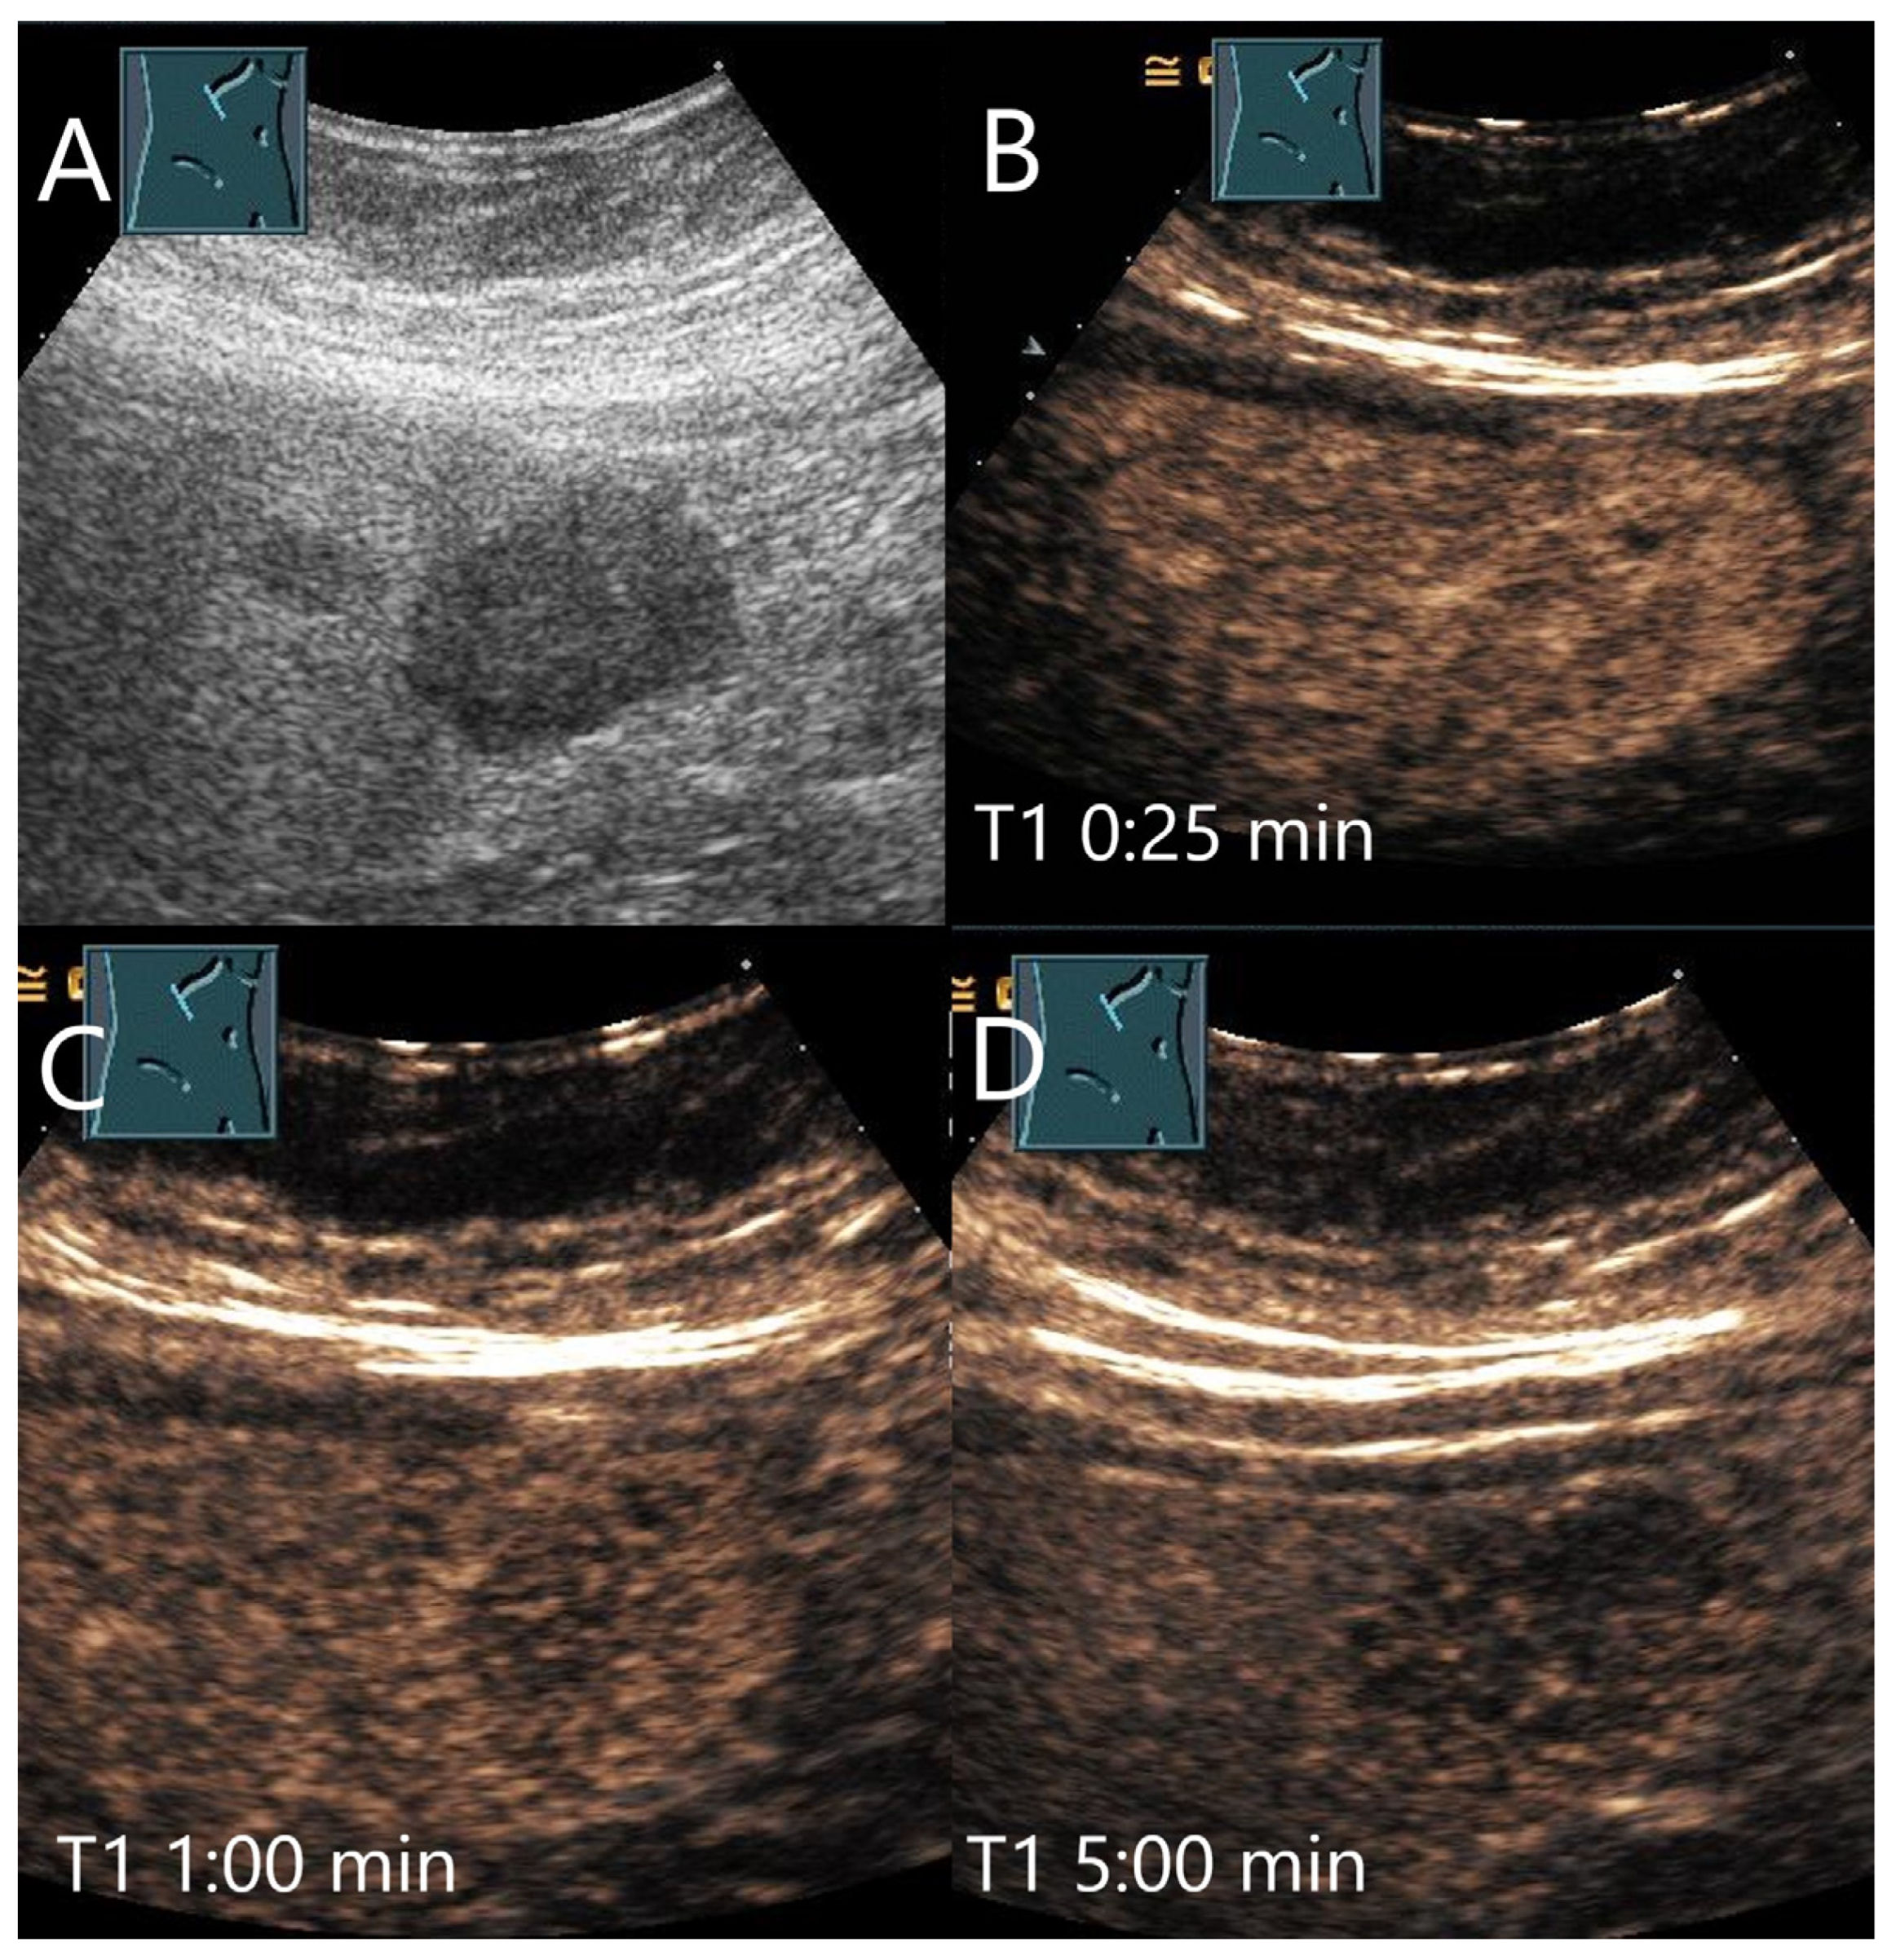

| FNH | Isoechoic, hypoechoic, sometimes hypoechoic rim. | Wheel spoke pattern, central artery, rarely peripheral artery and wheel. spoke pattern. Centrifugal filling | Hyperenhancement to isoenhanced, central scare. | Fibrosis and vascular obliteration. |